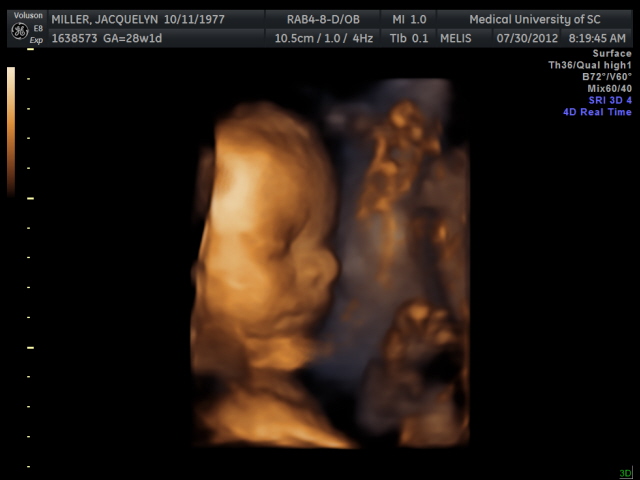

Sweet little brother!

Today's ultrasound appointment was sweet. Basically, it was just a growth check (don't get me started on how dumb I think that is) and he is currently measuring 61st percentile. Pretty normal. I expect that to go up the further along we get, but I'll take it for now! Everything else looked great. I was able to see him yawn a couple of times and stretch like crazy. So cute! My heart is full and I am very thankful.